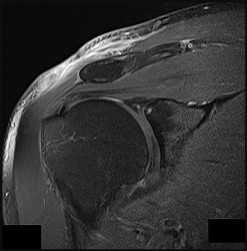

This patient has a dedifferentiated liposarcoma within a preexisting atypical lipomatous tumor. The imaging demonstrates a large fatty mass with increased internal septations proximally (the atypical lipomatous tumor) and a solid enhancing mass distally (the dedifferentiated portion). A biopsy reveals a high-grade liposarcoma. The other diagnostic responses do not reflect sarcomatous transformation of the lesion.